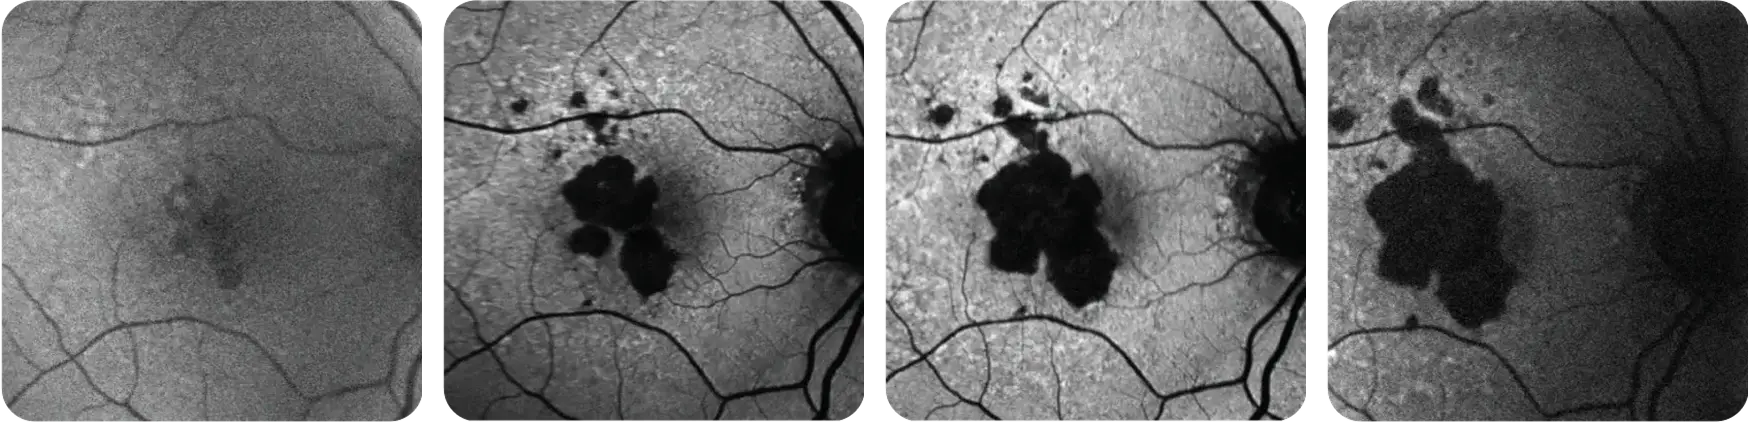

GA PROGRESSION CAN BE UNPREDICTABLE1

It may move faster than you think.

What may be happening to the retina

What may be happening to your patient’s vision

Representation of vision loss for illustrative purposes only.